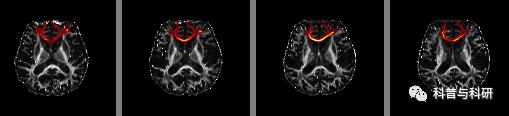

基于ROI-ROI的确定性纤维追踪实现与统计 |

1、弥散张量成像的配准 2、ROI的空间转换 3、用TrackVis进行纤维追踪 4、纤维束的量化统计与结果展示 |

基于ROI-ROI的概率性纤维追踪预处理 |

1、概率性纤维束跟踪的模型构建 2、基于Volume的概率性纤维束跟踪实现 |

5月23日 (周日下午)13:00-17:00 |

基于ROI-ROI的概率性纤维追踪统计 |

1、基于皮层的概率性纤维束跟踪实现 2、纤维束的量化统计与结果展示 |